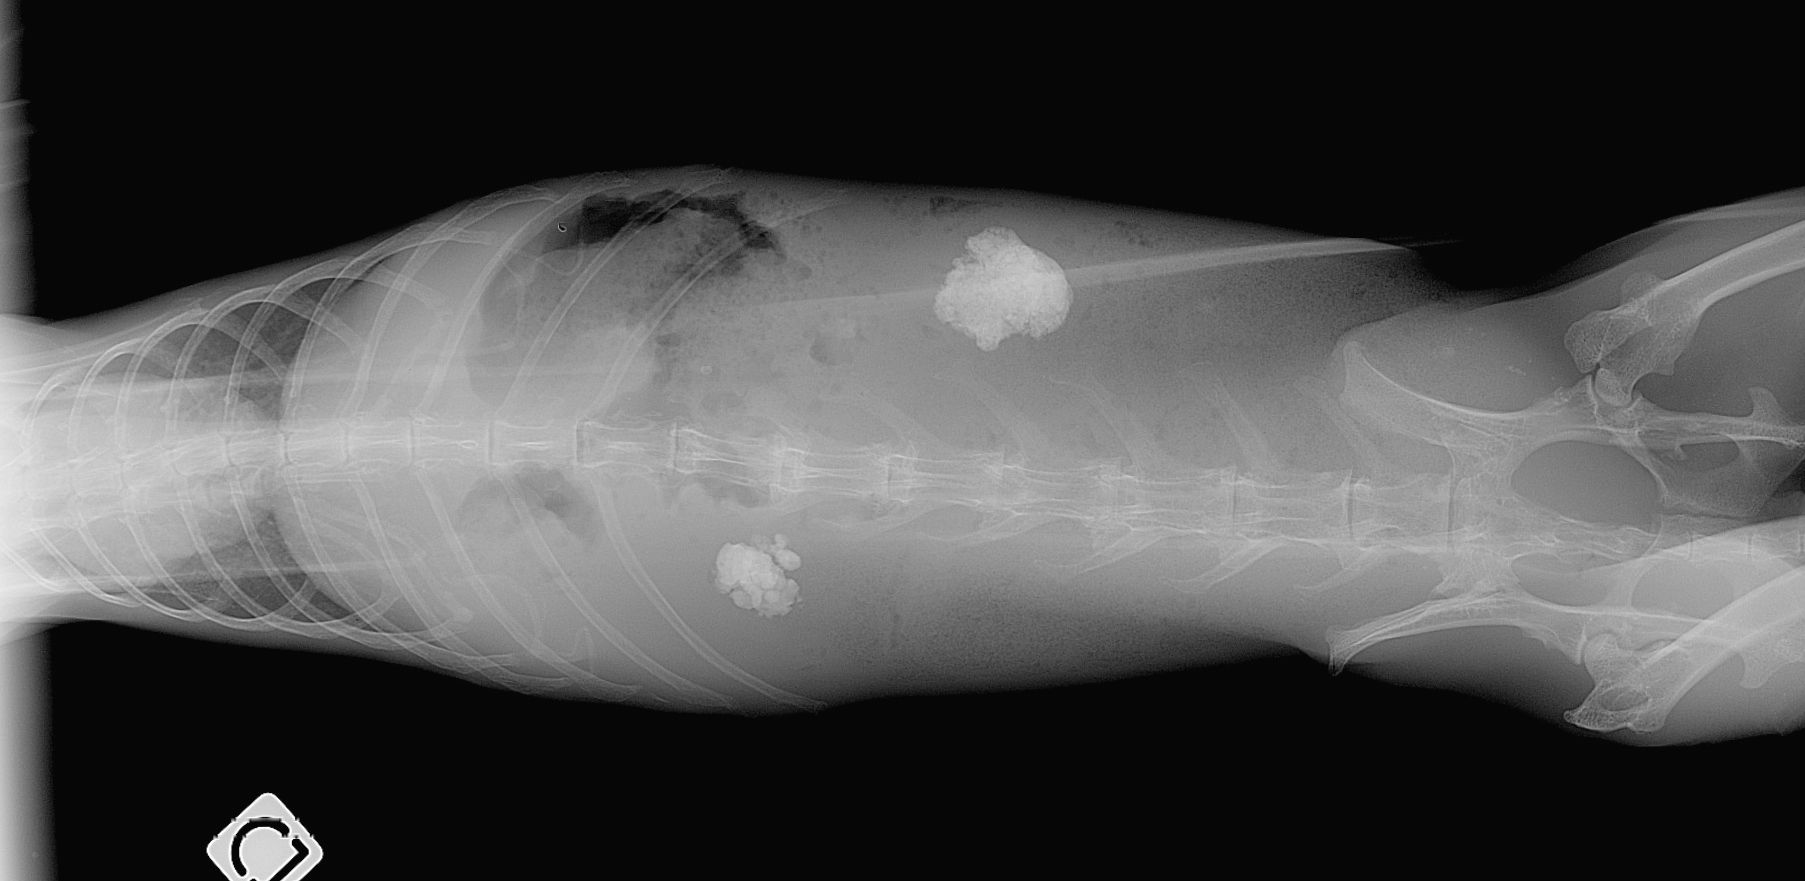

Le diagnostic est relativement aisé par radiographie. Cependant, toutes les sabloses ne sont pas nécessairement pathologiques. Un bilan complet associant prise de sang et échographie est recommandé. Le traitement passe par une amélioration de l'hydratation et des rectifications alimentaires. Cette sablose peut prédisposer aux calculs vésicaux, urétéraux ou rénaux.

Calcul vésical

Les calculs urinaires dans la vessie sont courants chez le lapin et le cobaye et ils sont également observés plus rarement chez les chinchillas. Ils peuvent être particulièrement délétères et causer une douleur intense lors de l'émission des urines et la présence de sang dans les urines. En cas d'obstruction urinaire (impossibilité d'évacuation des urines), il s'agit d'une urgence vitale absolue pour le lapin et les rongeurs.

Le diagnostic se fait par radiographie mais une échographie et une prise de sang sont recommandés pour exclure la présence d'autres calculs au niveau des uretères et des reins et aussi pour vérifier l'absence d'insuffisance rénale. Le traitement est quasiment toujours chirurgical, certains cas particulier peuvent être traité par endoscopie ou par traitement médical.